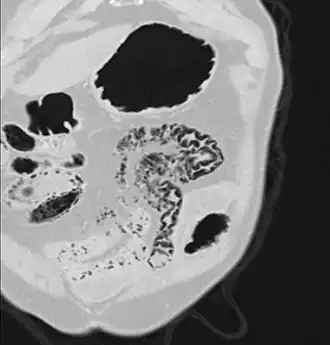

Pneumatosis intestinalis (also called intestinal pneumatosis, pneumatosis cystoides intestinalis, pneumatosis coli, or intramural bowel gas) is pneumatosis of an intestine, that is, gas cysts in the bowel wall.[1][2] As a radiological sign it is highly suggestive for necrotizing enterocolitis. This is in contrast to gas in the intestinal lumen (which is relieved by flatulence). In newborns, pneumatosis intestinalis is considered diagnostic for necrotizing enterocolitis, and the gas is produced by bacteria in the bowel wall.[3] The pathogenesis of pneumatosis intestinalis is poorly understood and is likely multifactorial. PI itself is not a disease, but rather a clinical sign. In some cases, PI is an incidental finding, whereas in others, it portends a life-threatening intra-abdominal condition.